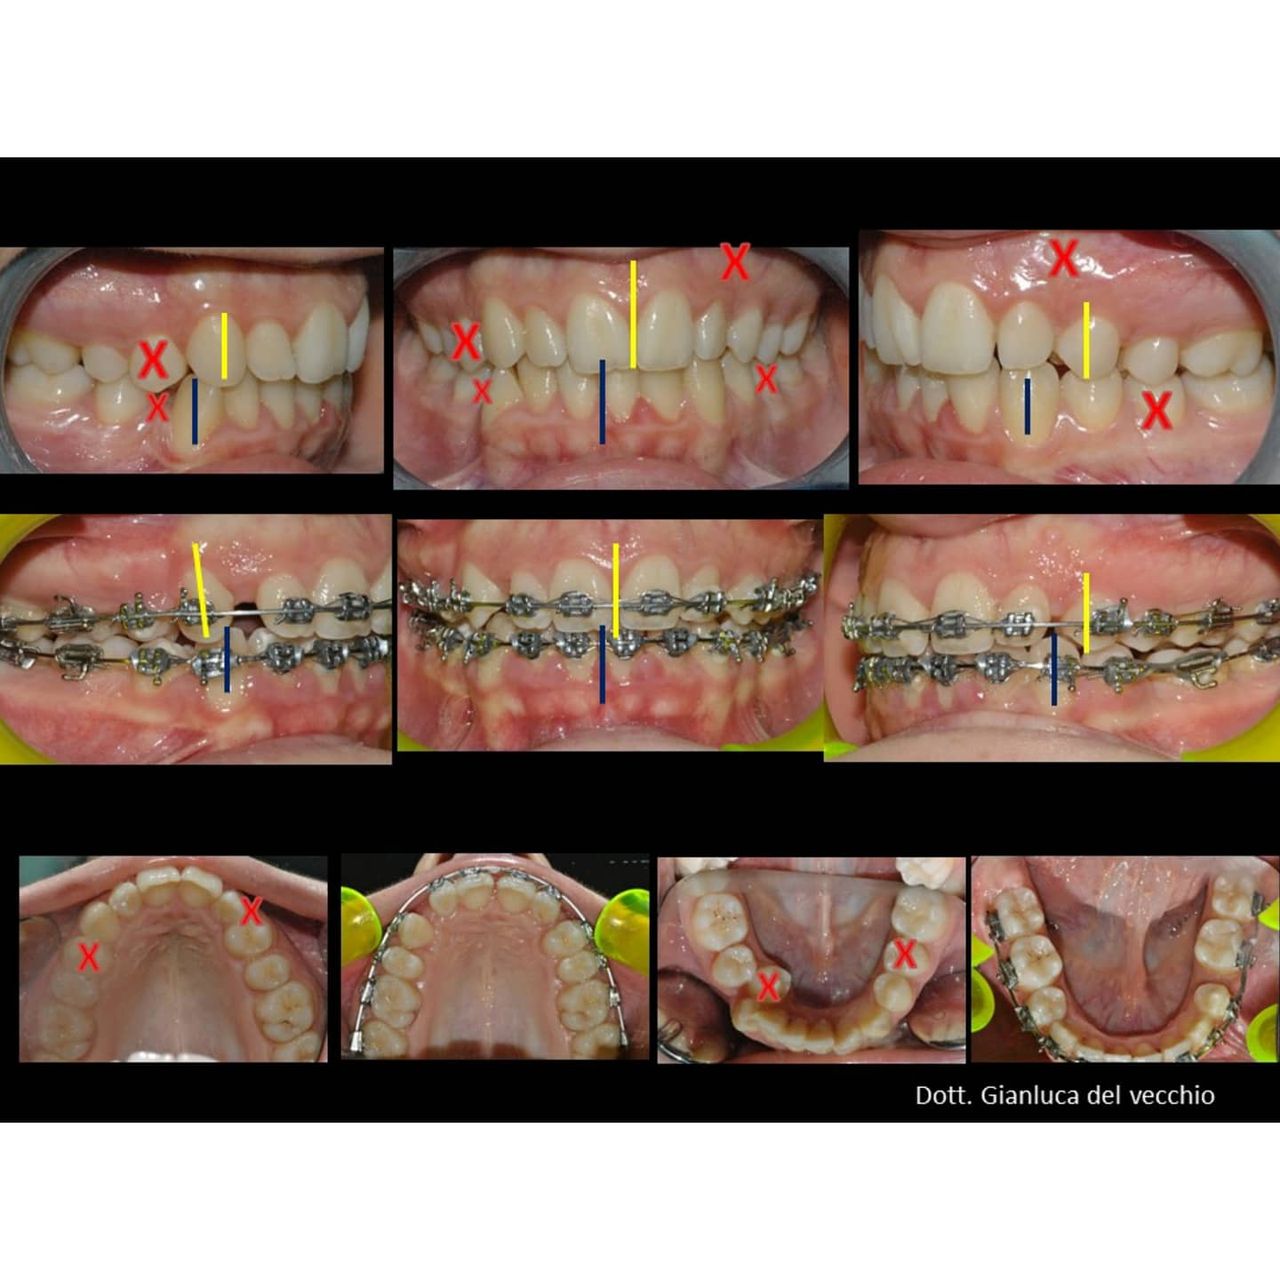

Il dottor Gianluca del Vecchio si occupa esclusivamente di ortognatodonzia, grazie anche alla collaborazione multidisciplinare di una équipe davvero entusiasmante e all’utilizzo di strumenti diagnostici e terapeutici all’avanguardia in ortognatodonzia. Particolare è la sua capacità di condurre i giovani pazienti ad affrontare, nella massima sicurezza emotiva e clinica, qualsiasi eventuale condizione di dolore derivante, ad esempio, da carie o da altre patologie, ma soprattutto di risolvere tutte quelle condizioni di “denti storti”, così spesso causa di disagio psicologico o di fenomeni deprecabili, quale il bullismo.

Queste le ragioni che consentono di trattare le malocclusioni, sia dei bambini che degli adulti, con protocolli scientificamente validati come i più veloci, affidabili e confortevoli.

Buonasera, desiderei sapere quali odontoiatri, nella mia regione, utilizzano la tecnica meaw /Sato, per malocclusioni dental-scheletriche. Grazie. (Daniele, Bari)

Salve, è una tecnica molto invasiva, con risultati ottimi ma spesso assolutamente sovrapponibile persino ad una terapia estetica, lo sapeva? Mi contatti per maggiori info